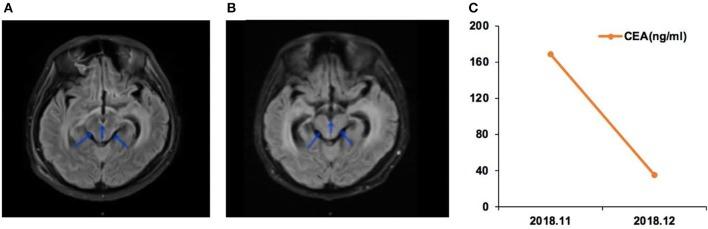

The significance of uncommon () mutations in patients with non-small cell lung cancer (NSCLC) and brain metastasis (BM) remains unclear. Cerebrospinal fluid (CSF) liquid biopsy is a novel tool for assessing mutations in BM. This study aimed to evaluate the mutations in patients with NSCLC and newly diagnosed BM and to examine the effect of EGFR tyrosine kinase inhibitors (TKI) on BM harboring CSF-tested uncommon mutations. This was a prospective study of 21 patients with NSCLC and BM diagnosed between 04/2018 and 01/2019. CSF was obtained to detect the BM mutations by next-generation sequencing. BM characteristics at magnetic resonance imaging (MRI) and EGFR-TKI response were examined. Of 21 patients with NSCLC, 10 (47.6%) had leptomeningeal metastasis (LM), while 11 (52.4%) had brain parenchymal metastasis (BPM); 13 (61.9%) had confirmed mutation-positive primary tumors. The uncommon mutation rate in CSF ctDNA was 33.3% (7/21). Among those with mutation-positive primary tumors, the rate of uncommon mutations in CSF was 53.8% (7/13). Uncommon mutations were more common in patients with LM than in patients with PBM (6/11, 54.5% vs. 1/10, 10%), and included G719A, L861Q, L703P, and G575R. TKI was effective for four patients with BMs harboring uncommon mutations. In patients with NSCLC and LM, the rate of uncommon mutation was high. The BMs with uncommon mutations seem to respond to EGFR-TKI treatment. CSF liquid biopsy could reveal the genetic profile of the BM and help guide treatment using small-molecule TKI.

非小细胞肺癌(NSCLC)合并脑转移(BM)患者中罕见的()突变的意义仍不明确。脑脊液(CSF)液体活检是评估BM中()突变的一种新型工具。本研究旨在评估NSCLC合并新诊断BM患者中的()突变,并研究表皮生长因子受体(EGFR)酪氨酸激酶抑制剂(TKI)对携带经CSF检测为罕见()突变的BM的影响。这是一项对2018年4月至2019年1月期间诊断的21例NSCLC合并BM患者的前瞻性研究。通过下一代测序获取CSF以检测BM中的()突变。检查了磁共振成像(MRI)时的BM特征和EGFR-TKI反应。在21例NSCLC患者中,10例(47.6%)有软脑膜转移(LM),而11例(52.4%)有脑实质转移(BPM);13例(61.9%)原发性肿瘤经确认()突变阳性。CSF循环肿瘤DNA(ctDNA)中的罕见突变率为33.3%(7/21)。在原发性肿瘤()突变阳性的患者中,CSF中罕见()突变的发生率为53.8%(7/13)。罕见()突变在LM患者中比在PBM患者中更常见(6/11,54.5%对1/10,10%),包括G719A、L861Q、L703P和G575R。TKI对4例携带罕见()突变的BM患者有效。在NSCLC合并LM的患者中,罕见()突变率较高。具有罕见()突变的BM似乎对EGFR-TKI治疗有反应。CSF液体活检可以揭示BM的()基因特征,并有助于指导小分子TKI的治疗。